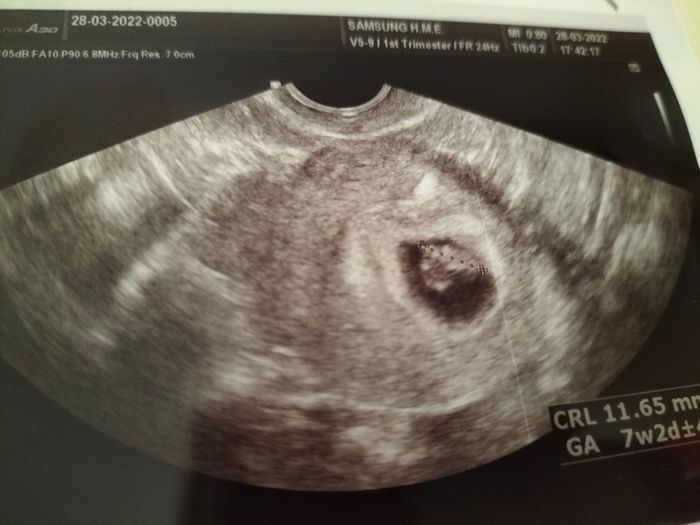

Salve a tutte, ho un’ecografia di 6+1, volevo chiedere secondo voi cos’è secondo il metodo Ramzi, l’ho confrontata con l’ecografia del primo figlio ed è uguale l’orientamento dell’embrione. È un’ecografia interna.